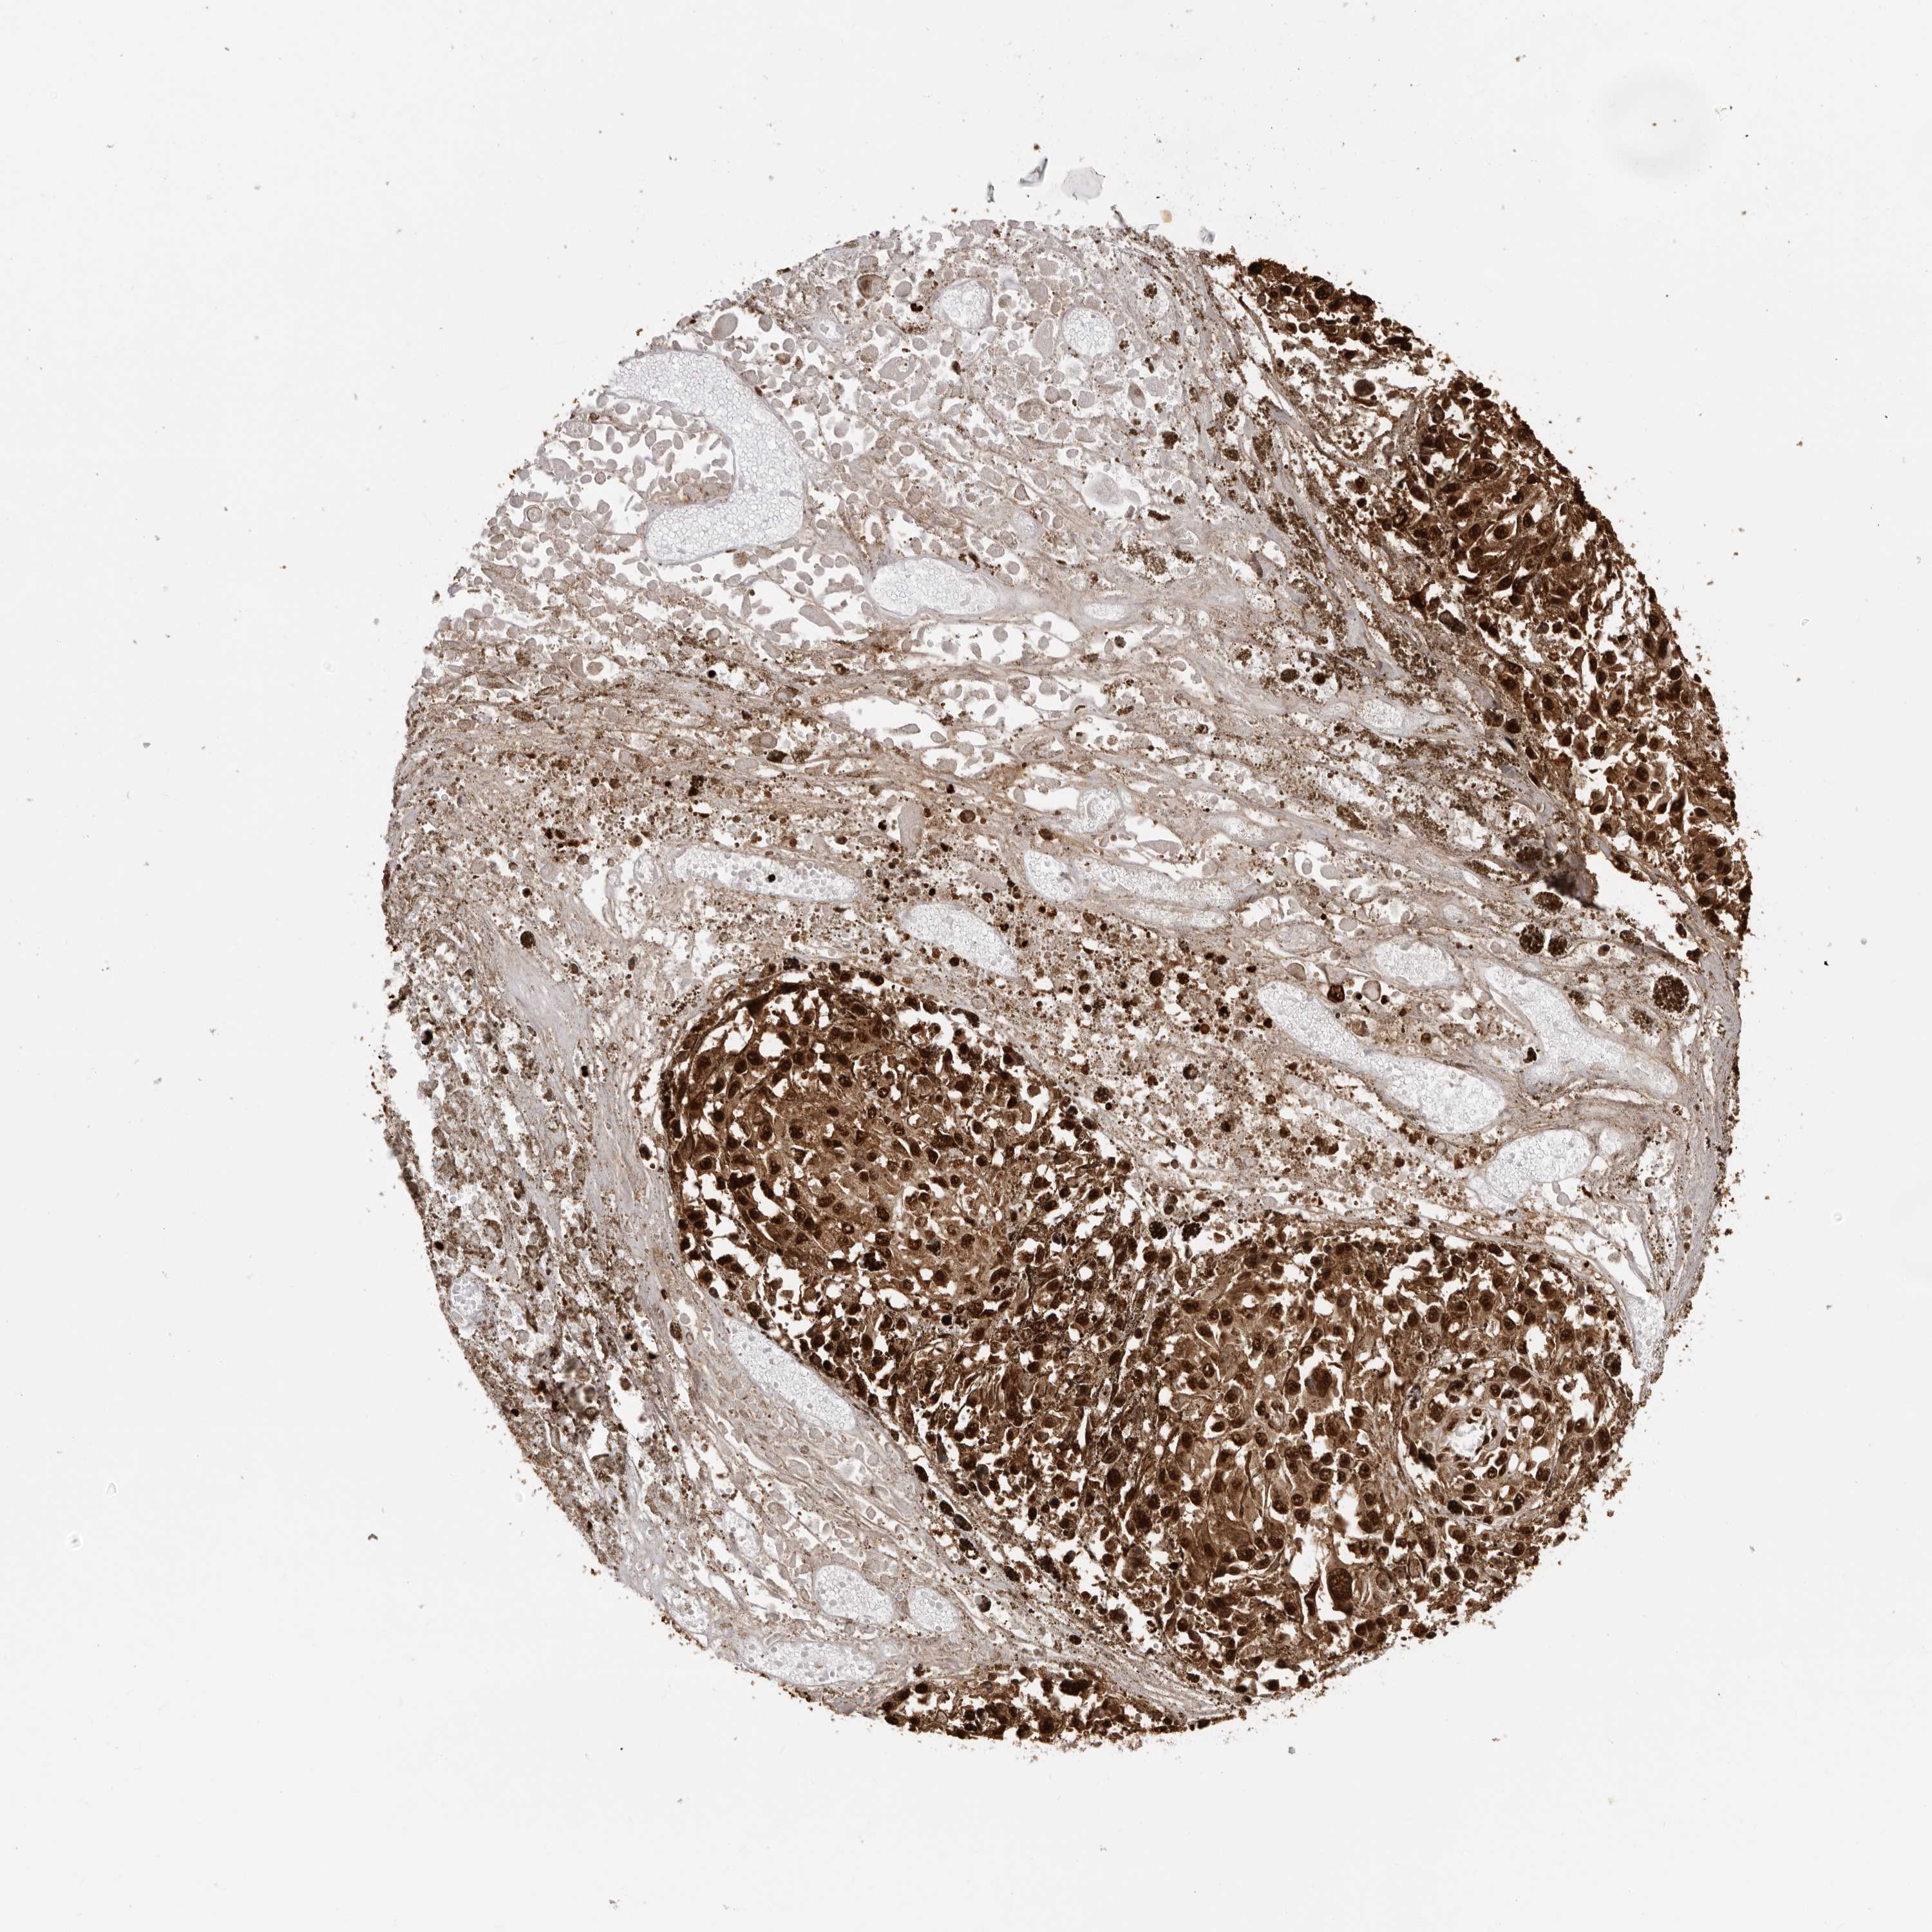

MELANOMA - Protein expressioni

A mouse-over function shows sample information and annotation data. Click on an image to view it in a full screen mode. Samples can be filtered based on level of antibody staining by selecting one or several of the following categories: high, medium, low and not detected. The assay and annotation is described here.

Note that samples used for immunohistochemistry by the Human Protein Atlas do not correspond to samples in the TCGA dataset.

Antibody stainingi

Antibody staining in the annotated cell types in the current human tissue is reported as not detected, low, medium, or high, based on conventional immunohistochemistry profiling in selected tissues. This score is based on the combination of the staining intensity and fraction of stained cells.

Each image is clickable and will lead to virtual microscopy that enables deeper exploration of all samples and also displays staining intensity scores, fraction scores and subcellular localization as well as patient and tissue information for each sample.

Antibody HPA024037

Antibody HPA065325

Antibody HPA074591

Antibody CAB025417

Staining

High

Medium

Low

Not detected

Intensity

Strong

Moderate

Weak

Negative

Quantity

>75%

75%-25%

<25%

None

Location

Nuclear

Cytoplasmic/membranous

Cytoplasmic/membranous,nuclear

Malignant melanoma, NOS

Malignant melanoma, Metastatic site